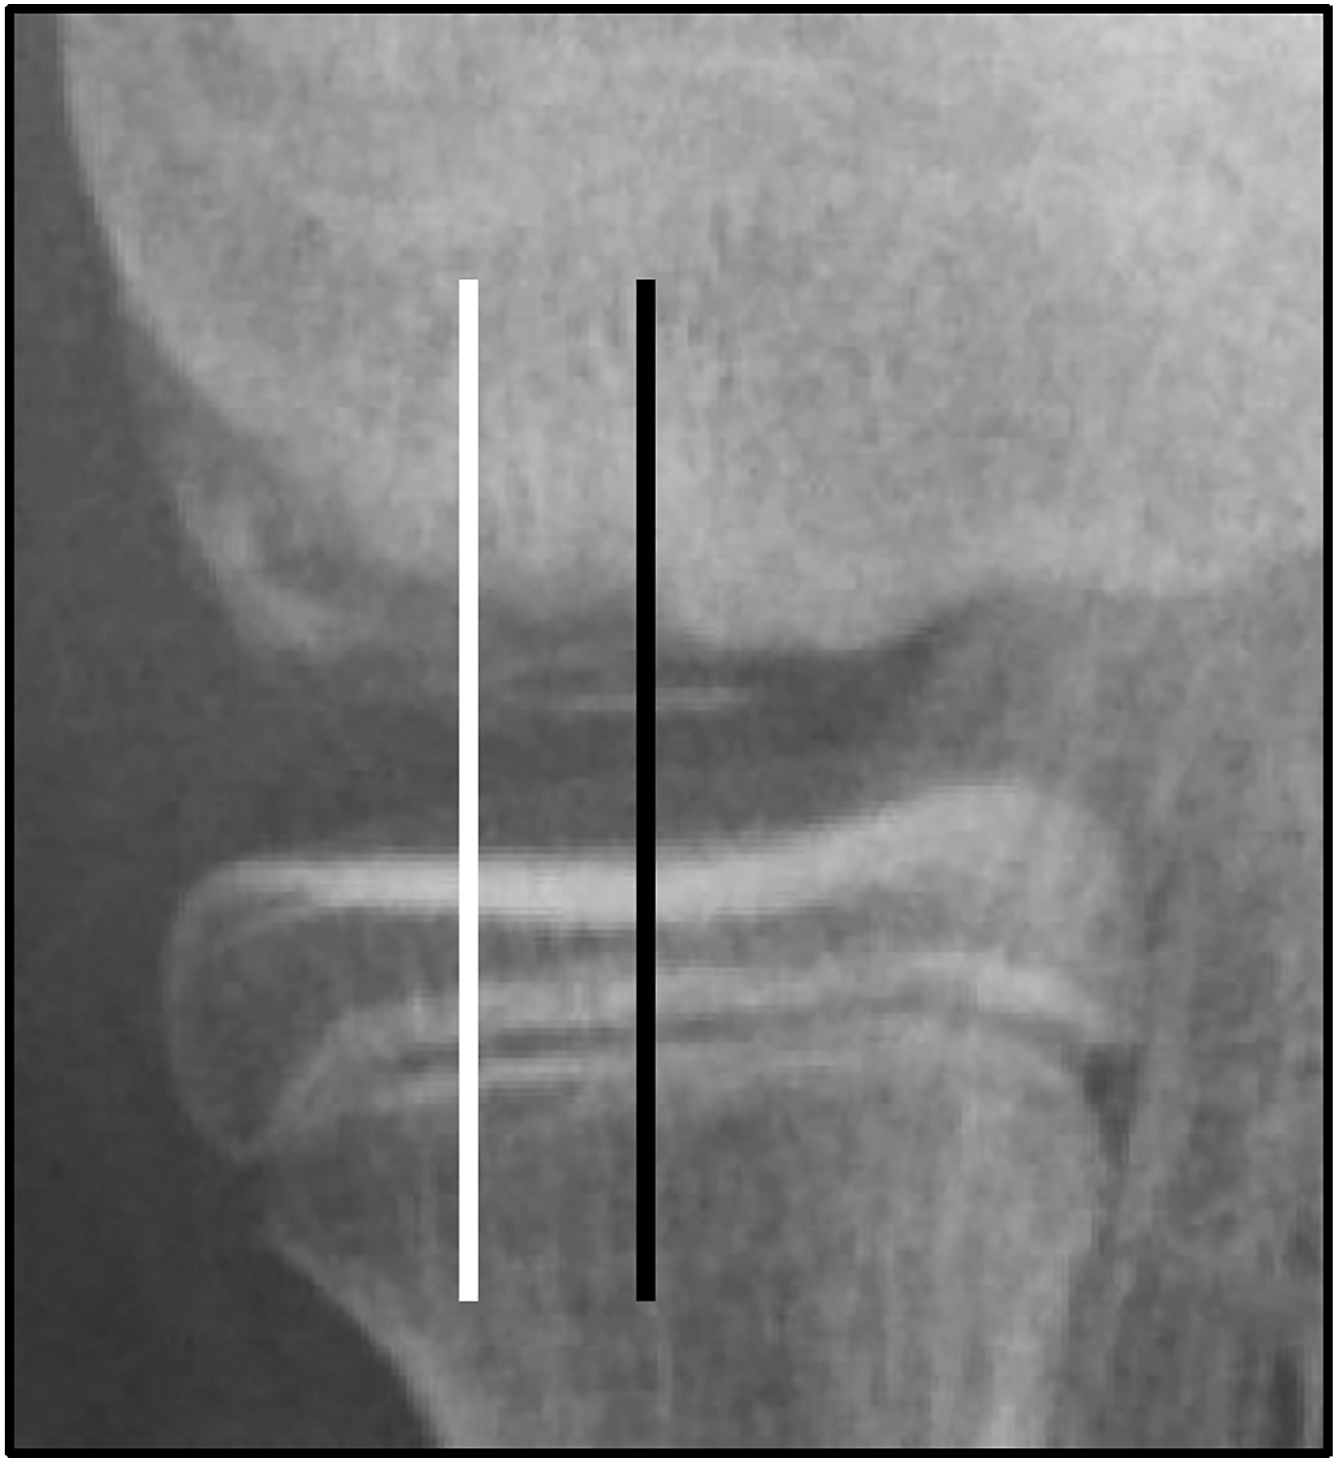

Initial workup begins with plain radiographs. While often initially normal and nondiagnostic, characteristic findings can include new periosteal bone formation, enthesopathy, endosteal thickening, cortical radiolucency and sclerosis, and even late fracture lines. , Early detection and diagnosis of OSF is imperative as prior literature has demonstrated a statistically significant difference in return time to sport in athletes when the stress injury was diagnosed within 3 weeks of symptom onset (return time 10.4 vs 18.4 weeks). Lateral radiographs with the humerus internally rotated 20° (“hand down lateral”) may enhance visualization of the posteromedial olecranon ( Fig. 7 ). , If stress injury is suspected but radiographs appear normal, advanced imaging with CT, MRI, and 3 phase bone scan may be helpful with early diagnosis. CT scan is often useful in identifying cortical abnormalities and early signs of fatigue damage. It should be performed on a minimum 128 slice scanner with true axial, sagittal, and coronal alignments and may also be used to follow stress reaction healing postoperatively. Bone scintigraphy is quite sensitive for early detection of stress reactions within 3 to 5 days after symptom onset due to its capacity to detect areas of subtle osseous turnover and stress remodeling. However, MRI has remained the gold standard for diagnosis due to its enhanced sensitivity and specificity. With its sequencing-dependent capacity to detect early bone edema, it also provides a more comprehensive evaluation of the bone and surrounding soft tissue, making it especially critical in throwers when considering and evaluating the relationship between olecranon stress injury and MUCL damage. , However, it is also important to note that MRI may provide a delayed positive or false negative especially in olecranon tip and sublime tubercle fractures. ,